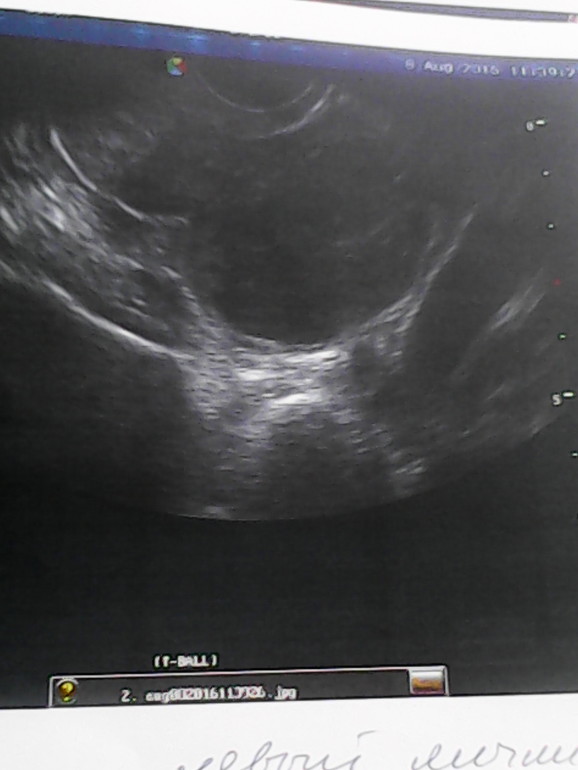

Посмотрите пожалуйста снимок с желтым телом это ведь оно?

сказал жт 14*9мм